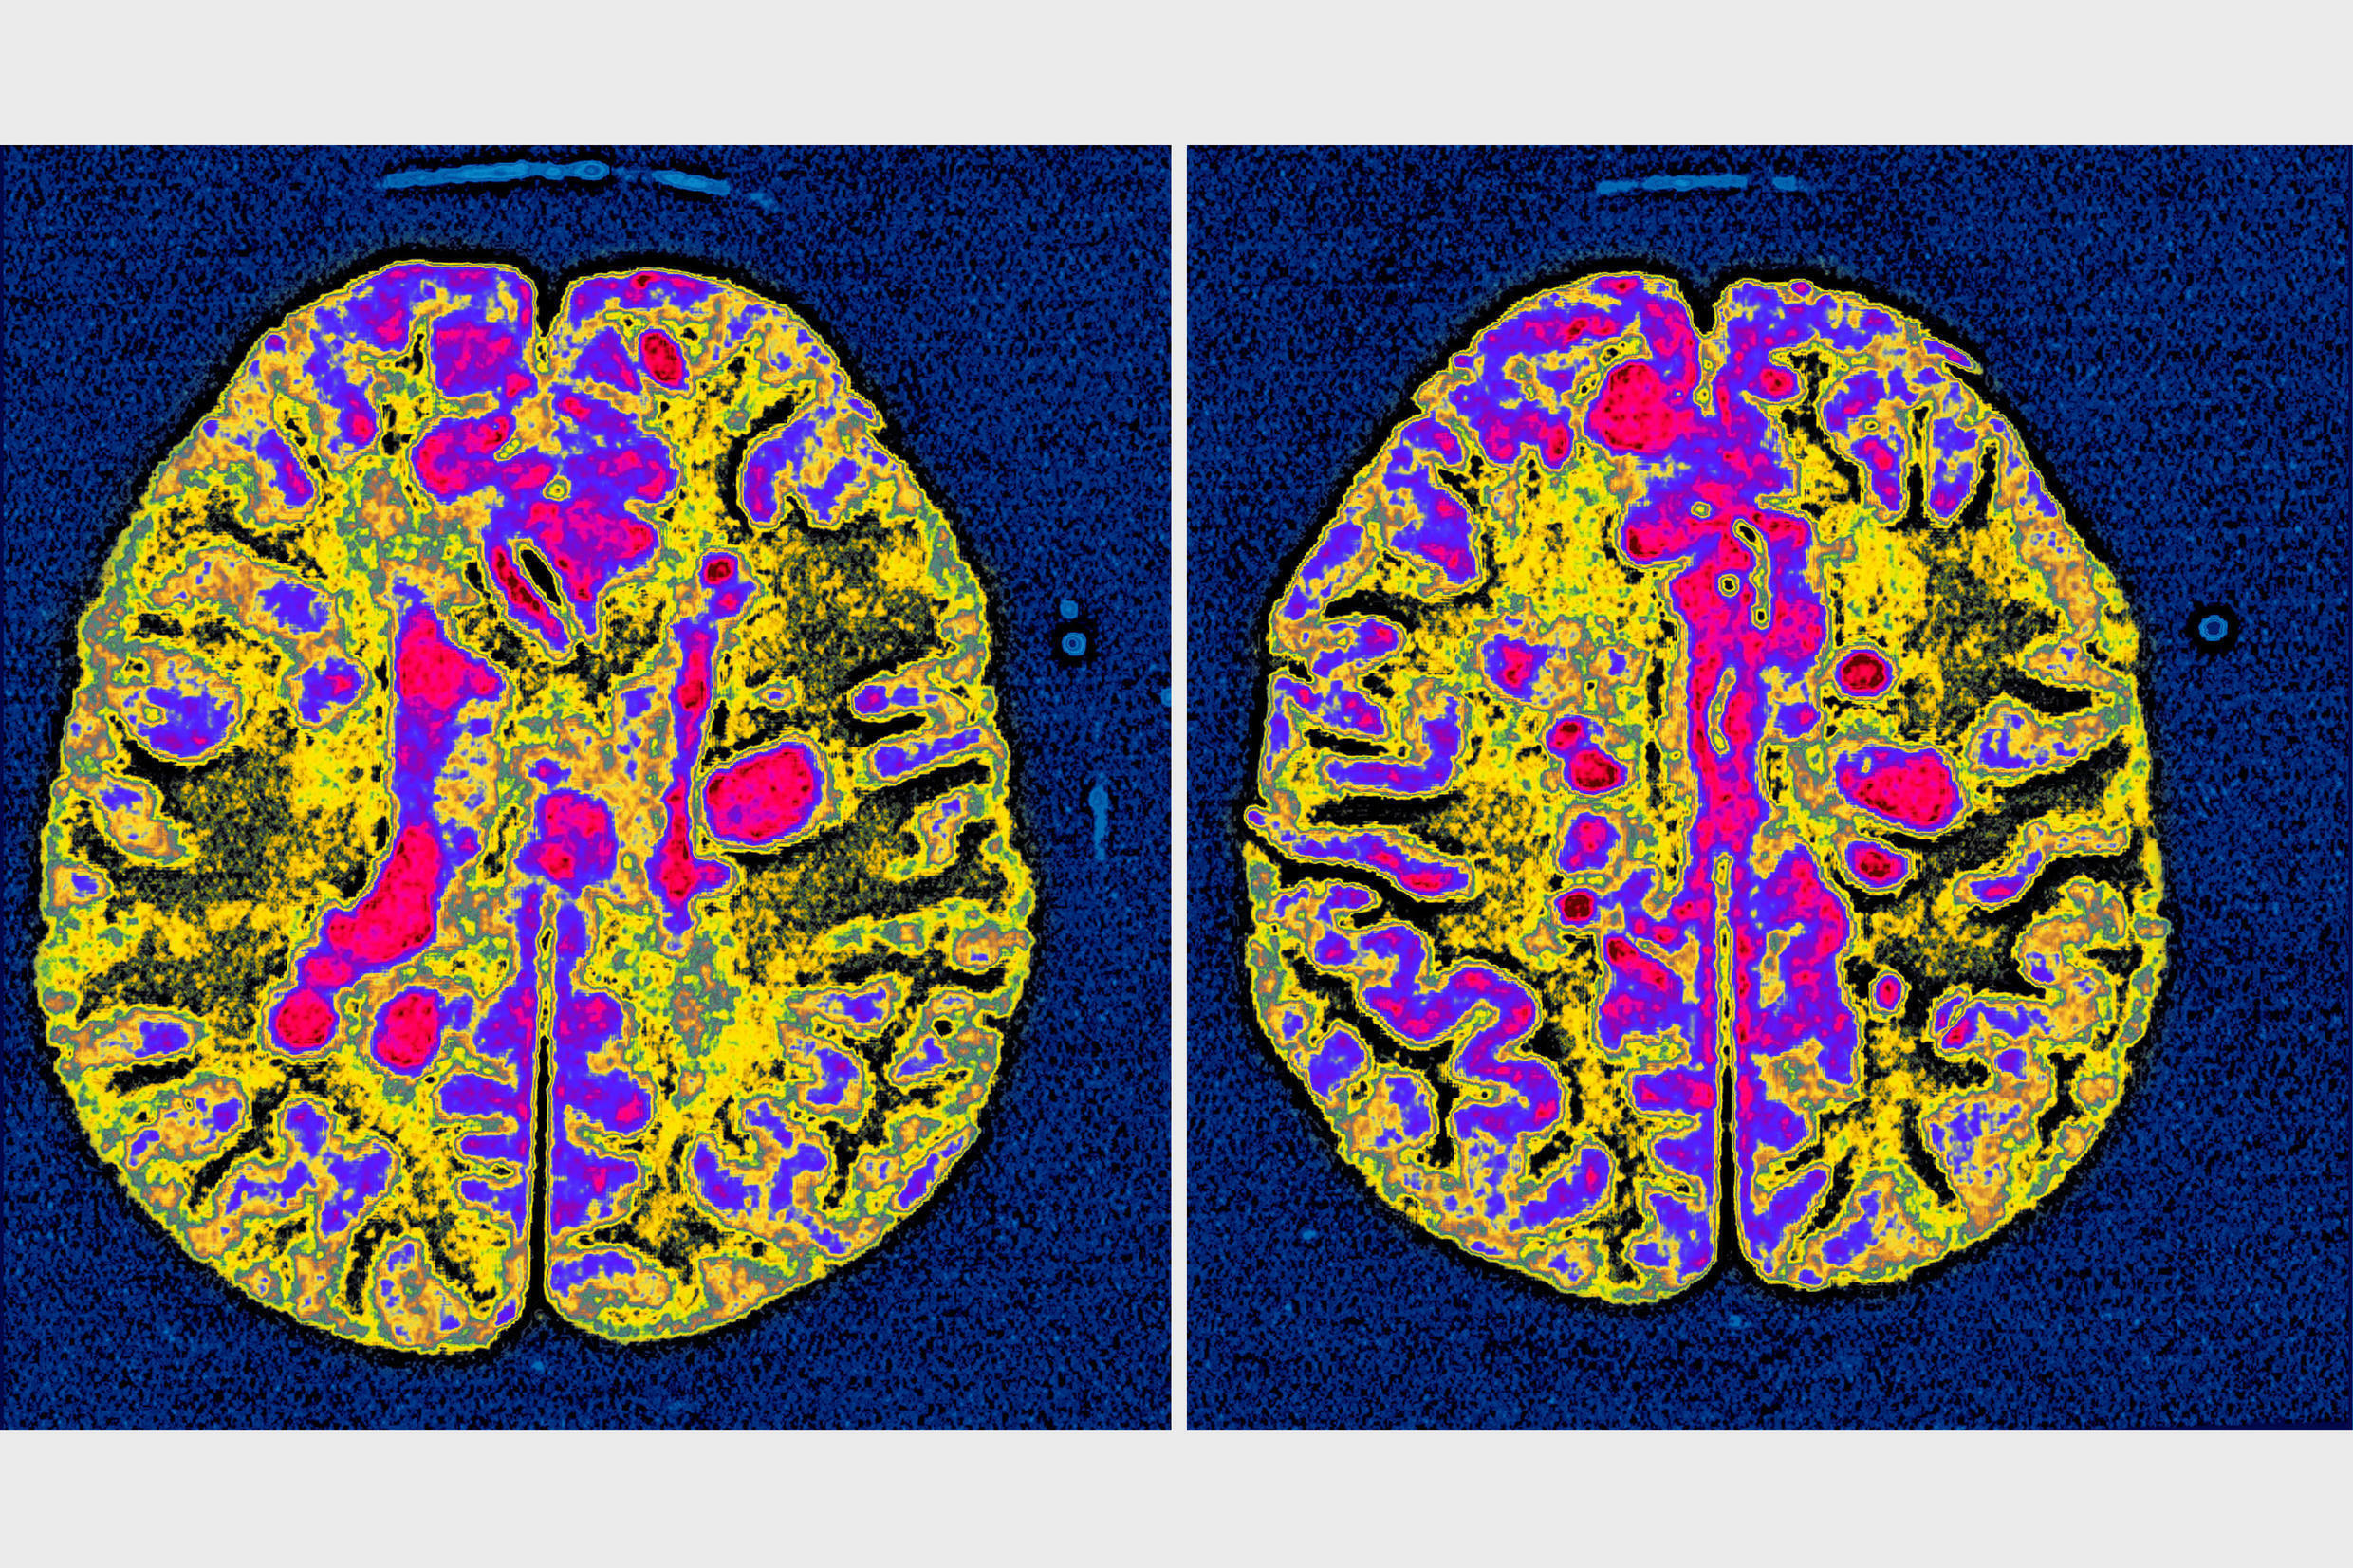

Alzheimer's disease researchers found that by removing brain immune